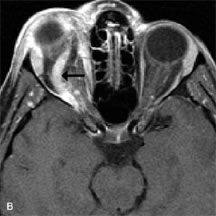

Breast carcinoma metastatic to the orbit has been demonstrated to be hypointense to the surrounding orbital fat on T1-weighted studies and hyperintense on T2-weighted images and has an affinity to the extraocular muscles (Fig. 20).50,64 The MRI characteristics of prostate carcinoma metastatic to the orbit have been described as involving the greater and lesser wing of the sphenoid, orbital roof, and optic canal. Diffuse bone hypertrophy with isointense or slightly hyperintense tissue on T1-weighted images represents the osteoblastic carcinomatous bone infiltration. Contrast enhancement is variable on T1-weighted and fat-suppressed images.65

Fig. 20. A. T1-weighted MR scan demonstrates nodular enlargement of both medial rectus muscles (arrows). B. T1-weighted fat-suppressed contrast-enhanced scan confirms the presence of small metnstatic deposits within the muscles (open arrows).